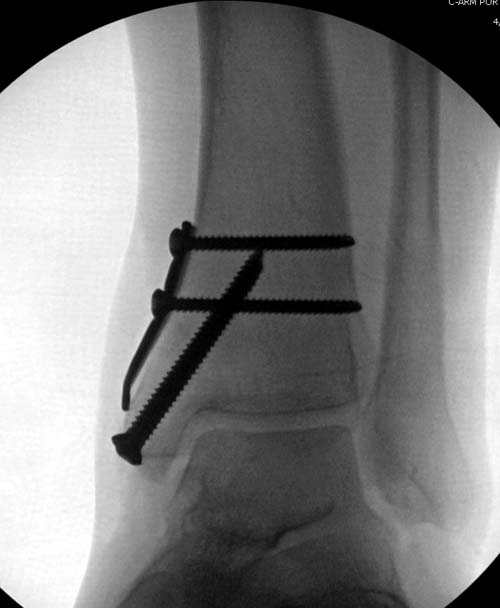

Артроскопия с дебридментом приносит облегчение, но огромные медиально-верхние дефекты надо замещать. Хирургический доступ через медиальную лодыжку, а для замещения применяют современные алломатериалы.

И пару дней назад провели операцию... А при огромных дефектах остеохондральный аллографт который выбирается по контуру тарана.